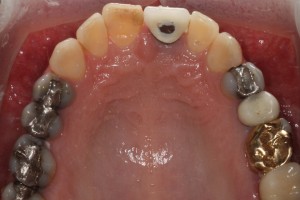

Powierzchnia okluzyjna zębów górnych – liczne wypełnienia amalgamatem, złoty onlay i 2 nieszczelne korony